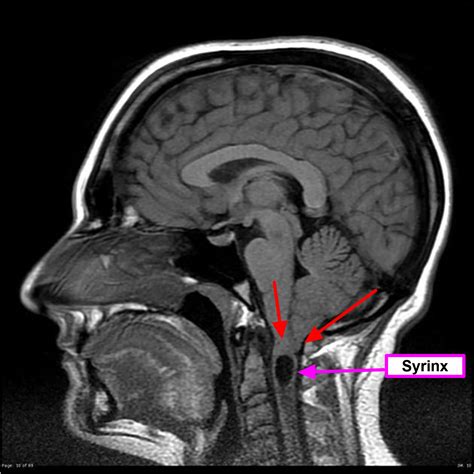

At its core, Chiari Type 2 involves the downward displacement of the cerebellar tonsils, the brainstem, and the fourth ventricle through the foramen magnum, which is the large opening at the base of the skull. This displacement creates a bottleneck effect that interferes with the normal flow of cerebrospinal fluid (CSF). Because this condition is developmental, it typically manifests in infants, as the structural abnormalities are present from birth.

The primary concern with this malformation is the obstruction of CSF circulation, which frequently leads to hydrocephalus—a condition where fluid accumulates in the brain, causing increased intracranial pressure. The structural interplay between the spine and the skull in these patients necessitates a highly coordinated medical approach involving neurosurgeons, pediatricians, and specialized therapists.

MRI (Magnetic Resonance Imaging) Provides detailed images of the cerebellum, brainstem, and spinal cord to assess the degree of herniation.